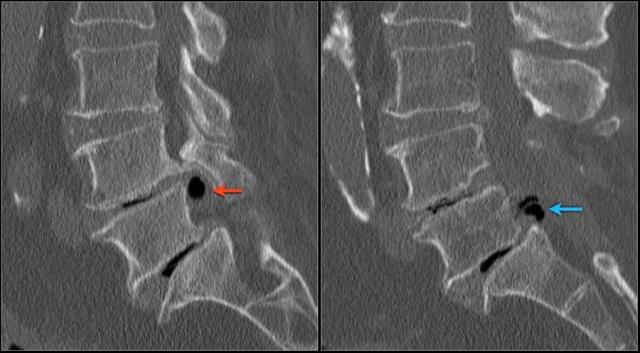

Hình ảnh chuỗi xung T1W mặt phẳng đứng dọc cho thấy một cấu trúc giảm tín hiệu rất thấp tại mức L4L5 (mũi tên) và tại mức L5S1.

Tiếp tục xem các hình ảnh chuỗi xung T2W.

Trên chuỗi xung T2W, cường độ tín hiệu cũng rất thấp.

Chụp CT được thực hiện để xác định liệu đây có phải là đĩa đệm thoát vị bị vôi hóa hay một xảo ảnh nào đó.

Tiếp tục xem các hình ảnh CT.

Tín hiệu thấp cuối cùng được giải thích là do hiện tượng chân không (vacuum phenomenon) gây ra bởi khí nitơ trong đĩa đệm thoát vị tại cả mức L4L5 (mũi tên đỏ) và mức L5S1 (mũi tên xanh dương).